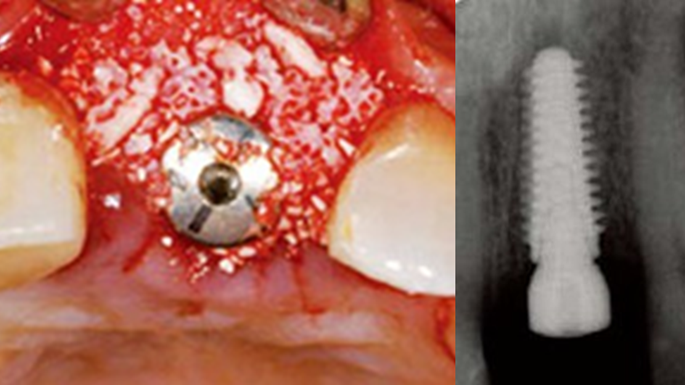

Clinical case: Bone filling into the bottom of deepest thread at 8.0mm AnyRidge fixture

- Courtesy of Dr. Kwang Bum Park -

AnyRidge, Knifethread ,extraction socket, ,initial stability ,Allograft, ,osseointegratio ,Dr. Kwang Bum Park, , Mandibular, Single replacement, AnyRidge, Mega-oss,

Implant system-AnyRidge, Regeneration-Mega-Oss

Immediate functional loading of single implants: a multicenter study with 4 years of follow-up./J Dent Res Dent Clin Dent Prospect 2018; 12(1):26-37 | doi: 10.15171/joddd.2018.005